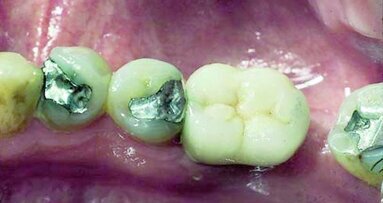

Afin de discuter de l'avenir de la dentisterie, nous devons d'abord regarder l'histoire de l'utilisation du mercure en dentisterie. Le mercure porte le ...